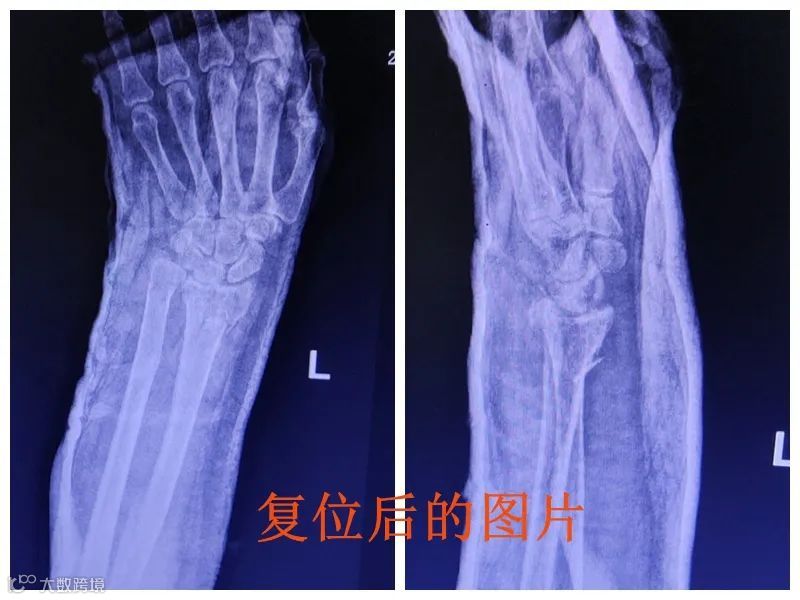

当晚,患者在家人陪同下来到市人民医院急诊科就诊,医生发现患者左手腕部肿胀,左手腕错位弯曲,于是进一步拍片检查受伤情况。经左腕关节DR拍片结果显示骨折严重:左桡骨远端骨折,左尺骨茎完全性骨折、骨折远端移位。

经过医生手法复位,将错位的骨折部位对接好,加上石膏外固定,固定好手腕部后,患者左手五指已能够活动,“手法复位固定后,起码要6-8周

手法复位后患者复查左手腕部DR,拍片显示骨折位置对位、对线较好。医生在此提醒广大市民,雨天出行注意安全,以免受伤。